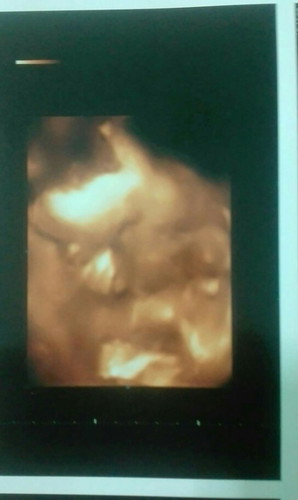

ความผิดพลาดที่แสนงดงาม💗💗

บ้านนี้29w ได้ลูกชายจ้าา